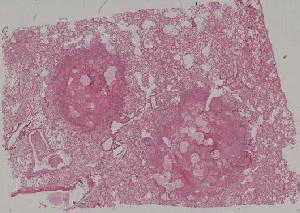

71. Acute transplant rejection of kidney